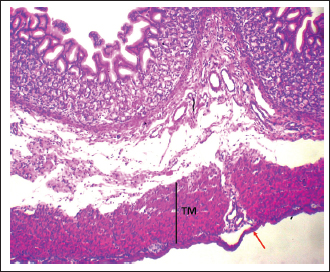

Fig. 7. Shows the pyloric zone in a neonatal dog: Tunica Muscularis (TM), and serosa (red arrow). H&E stain X40.

The pyloric region was characterized by short, straight, unbifurcating folds that overlapped invaginations of the gastric crypts. Pits in this region were deeper than those in the cardiac and fundic regions. The lining was made up of simple columnar epithelium with an epithelial height of 16.46 ± 1.41 µm (Fig. 6) (Table 1). The lamina propria contained vascular connective tissue disseminated with pyloric glands (Fig. 8). The lamina propria thickness was 122.44 ± 8.55 µm, and the mean number of pyloric glands was 20.71 ± 2.66 (Tables 1 and 2). Beneath the lamina propria, the muscularis mucosa was composed of smooth muscle fibers organized into inner circular and outer longitudinal layers, with a mean thickness of 23.11 ± 1.54 µm (Fig. 7). Tunica submucosa was constituted of loose connective tissue containing blood and lymphatic vessels, collagen fibers, fibroblasts, and adipocytes. The muscularis externa contained two layers of smooth muscle fibers: an inner thick circular layer and an outer thinner longitudinal layer. The tunica submucosa and muscularis externa thicknesses were 103.74 ± 2.44 µm and 201.42 ± 14.77 µm, respectively (Table 1). The outermost layer was the serosa, which was composed of mesothelium and loose connective tissue with a mean thickness of 30.42 ± 3.56 µm (Table 1). Mucous-secreting cells formed the majority of this cell population, and there were few parietal cells, averaging 0.55 ± 0.87, and chief cells were not present (Table 2). Mucous-secreting cells were pyramidal in shape with basally placed nuclei (Fig. 8).